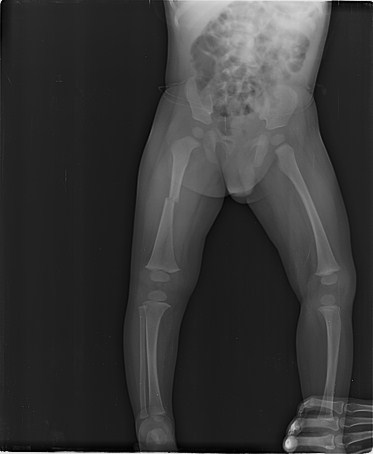

AI-Powered Fracture Detection & Classification

Upload X-ray images via drag-and-drop or select sample images for AI-powered fracture analysis.

Get instant AI diagnosis with confidence scores and medical recommendations in 5-10 seconds.

Review detailed findings and recommendations in the interactive canvas sidebar.

Advanced AI medical imaging tool developed at West Visayas State University for orthopedic fracture detection and classification.

Research-focused X-ray analysis system designed to assist medical professionals in diagnostic imaging.